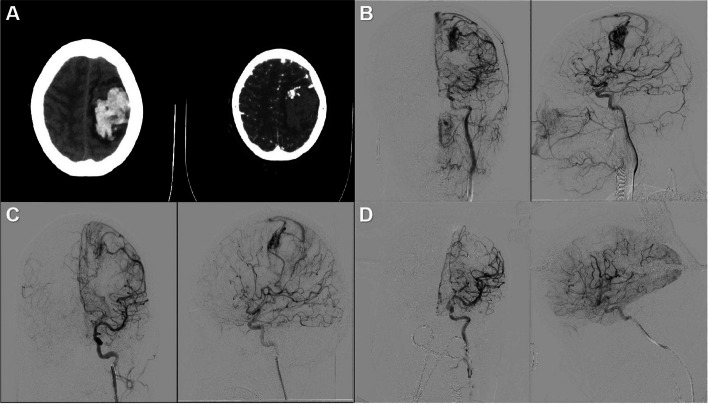

Background: Precise diagnosis and rapid treatment for acute complex intracranial hemorrhage (ICH) are crucial. The neurosurgical hybrid operating platform integrates traditional open neurosurgery operating room functionalities with endovascular therapy capabilities and is developing in the neurosurgical practice. However, its effect on the emergent complicated neurovascular cases needs pilot exploration.

Methods: In this prospective study, a total of 103 cases of both spontaneous and non-spontaneous ICH were consecutively recruited between June 2019 and June 2023. Demographic data, including age, gender distribution, and types of hemorrhage, were collected. Surgical interventions were tailored based on DSA, including spontaneous and non-spontaneous hemorrhages. Functional outcomes were assessed using the modified Rankin Scale (mRS) preoperatively and postoperatively.

Results: Over the study period from June 2019 to June 2023, a cohort of 103 ICH cases underwent emergency hybrid surgical treatment utilizing the E-HOPE platform. Among these cases, 88 were classified as spontaneous ICH, while 15 were non-spontaneous. The mean age at diagnosis for the entire cohort was 54.0 ± 3.7 years, with a slight predominance of male patients. Spontaneous ICH encompassed a diverse spectrum of etiologies, including arteriovenous malformations, aneurysms, arteriovenous fistulas, cavernous malformations, moyamoya disease, and cryptogenic hemorrhages. Surgical interventions were tailored to address the specific pathology. Notably, improvements in mRS scores were observed in a majority of cases, with some patients experiencing stabilization or deterioration postoperatively. Non-spontaneous cases (n = 15) were primarily iatrogenic (n = 13) due to tumors adjacent to the internal carotid artery, necessitating stent graft deployment. Surgical approaches, including stent graft deployment and middle meningeal artery embolization, were effective in managing these cases. Postoperative functional outcomes varied depending on the nature of the hemorrhage, with a subset of patients demonstrating improvement in mRS scores while others showed no significant change.

Conclusions: Emergency hybrid surgical treatment utilizing the E-HOPE platform offers promising outcomes for ICH patients. Tailored surgical approaches result in favorable postoperative functional outcomes, highlighting the importance of a multidisciplinary approach in managing these complex cases.